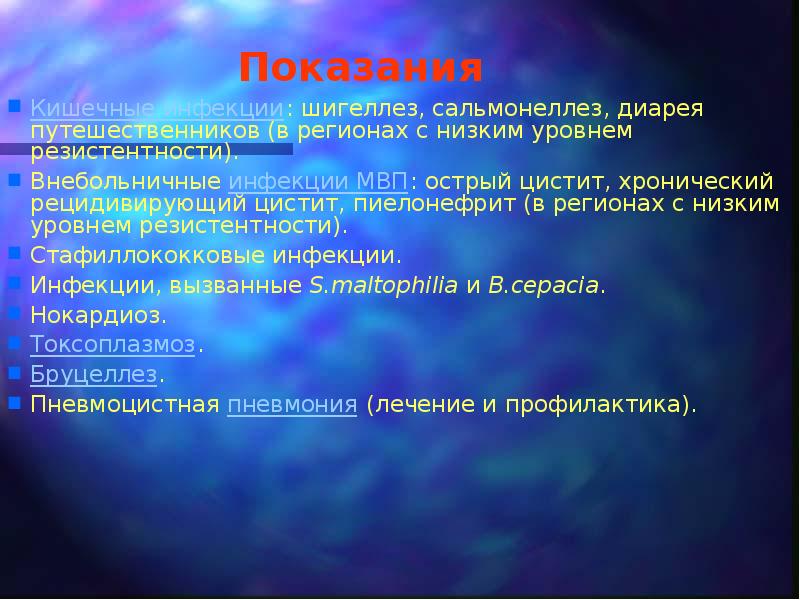

Острая внебольничная пневмония по МКБ-10: признаки и примеры